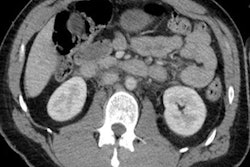

Visceral injuries and abnormalities often are readily identified using CT, but hypovolemic shock is less common and harder to diagnose, according to Irish researchers, who think it's vital to bear in mind how CT findings can allow correlation of imaging studies to the pathophysiological response to hypovolemic shock.